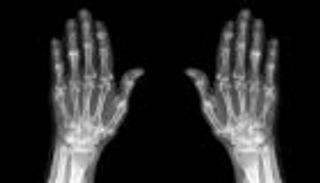

ومع الإصابة بهشاشة العظام يرتفع خطر التعرض للسقوط، ومن ثم الإصابة بكسور، مما يتسبب في تقييد الحركة.